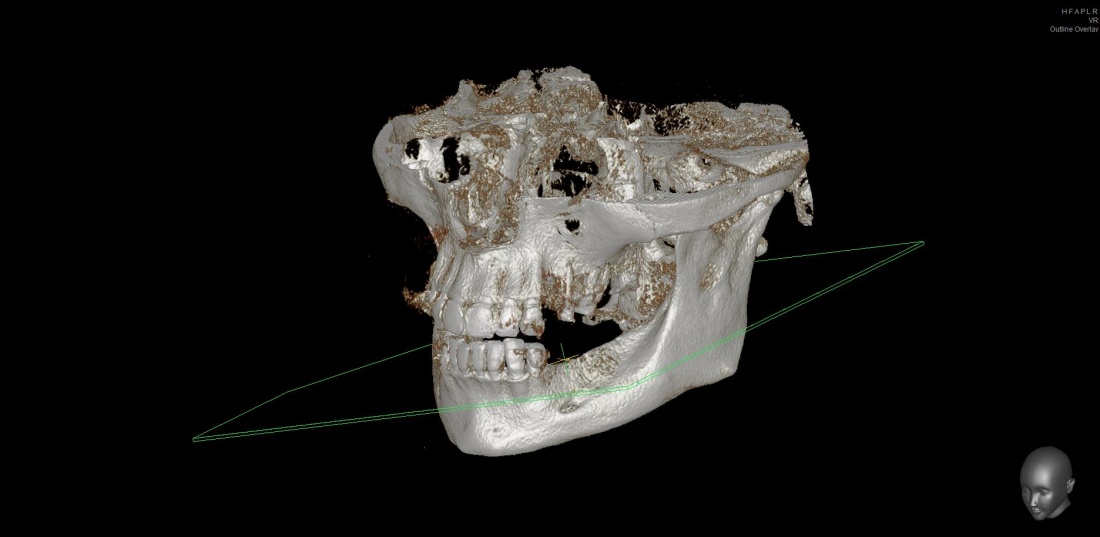

Простой. Надежный. Дешевый. Способ остеопластики.